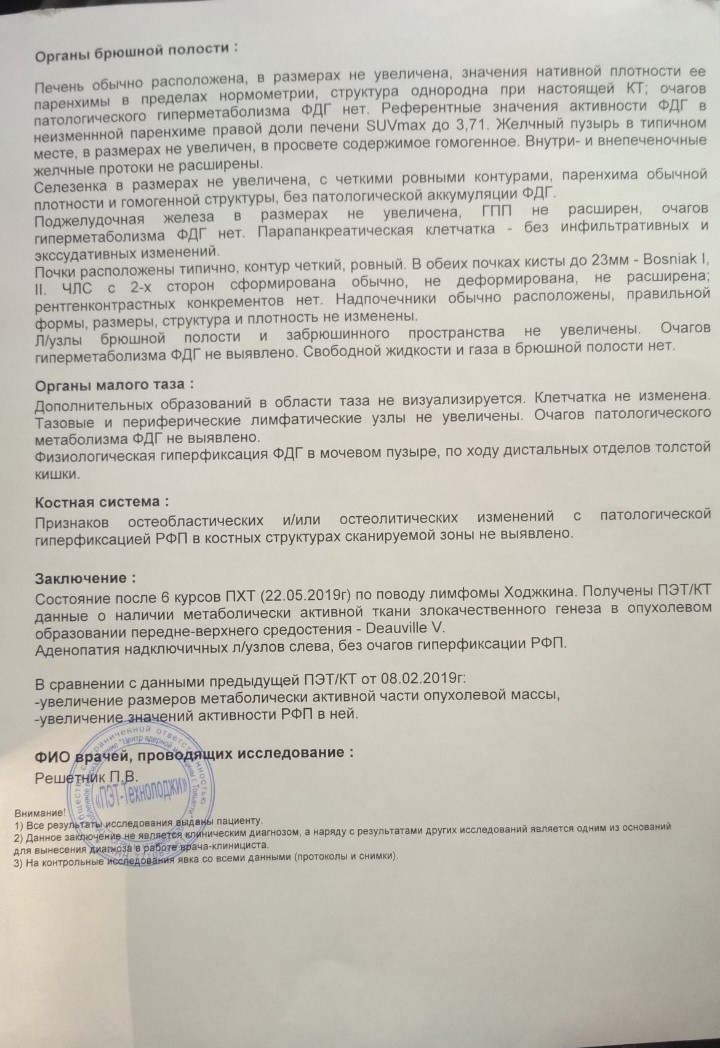

Диагностика лимфомы Ходжкина с помощью ПЭТ и КТ

Раздел: Светлые идеи